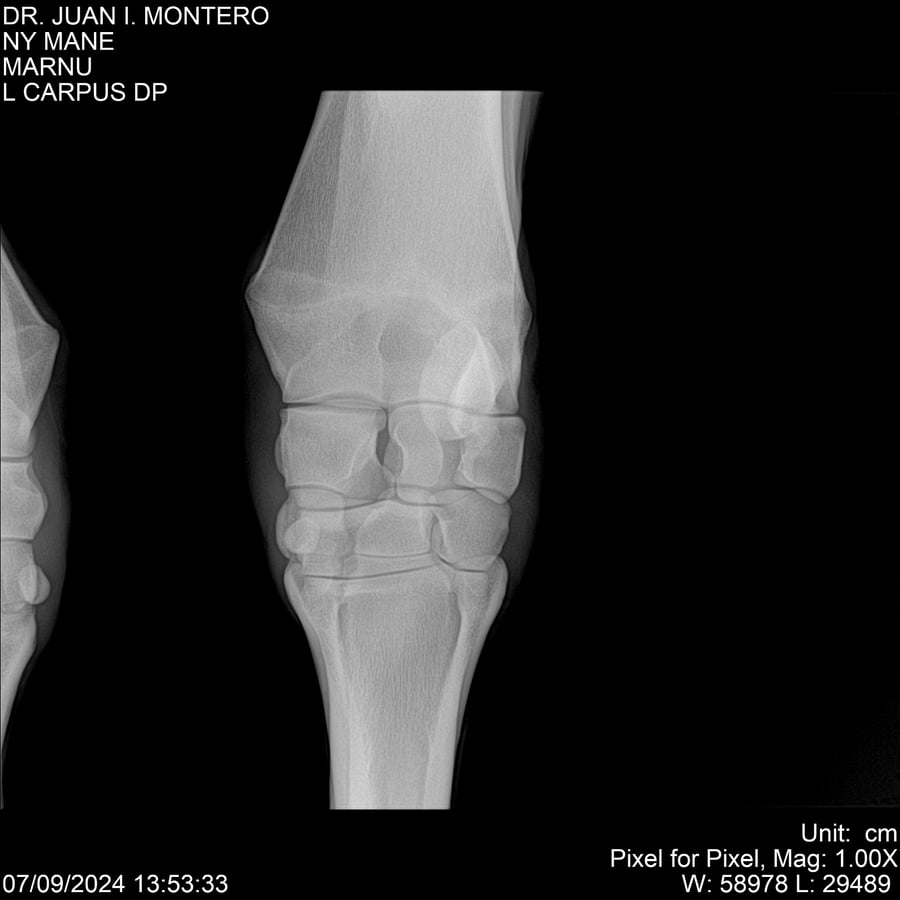

LOTE 20, NY MANE Lote Anterior Volver al remate Lote Siguiente Ficha Contacto Montevideo - Ficha del Lote Identificador: #282520 Categoría: Yeguarizos 76 Visualizaciones ClicData Contacto Empresa: Abelenda N. R., Walter Hugo Nombre*: Teléfono* : E-mail* : Mensaje Enviar Registrese gratis Este contenido Exclusivo está disponible sólo para usuarios registrados Ingresar